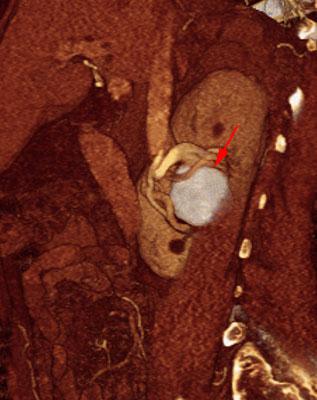

Aneurisma de arteria renal en monorreno

VR seccional. Visión sagital izquierda. AngioTC renal mostrando un aneurisma renal calcificado de la arteria renal derecha (flecha) a nivel del seno renal